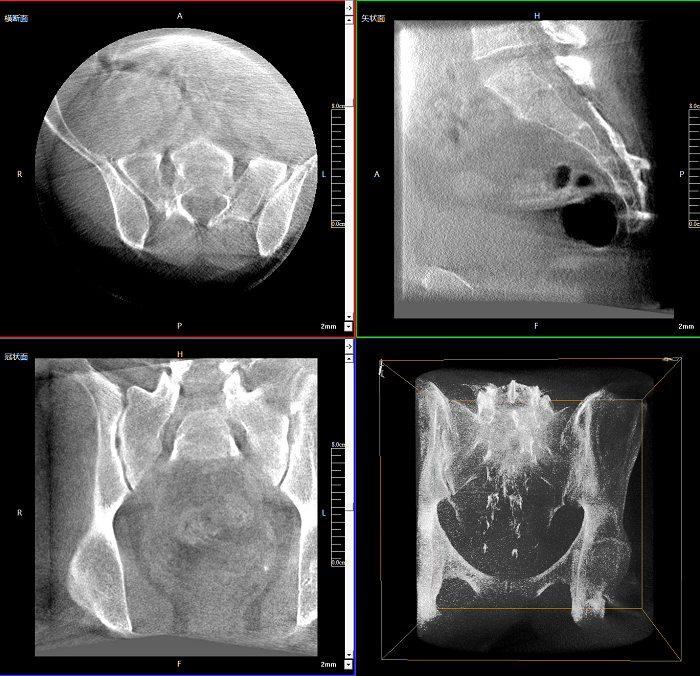

三維成像 全面觀(guān)察

任意視角、任意切面觀(guān)察

術(shù)中實(shí)時(shí)生成橫斷面、矢狀面、冠狀面及三維影像,可在任意切面、任意角度評估植入物和解剖結構的相對位置。

術(shù)中CT檢查 減少翻修概率

通過(guò)術(shù)中三維影像的檢查,可以立即發(fā)現植入物的錯位,減少不必要的第二次手術(shù),減少并發(fā)癥概率以及感染風(fēng)險。

Clinical picture

臨床圖片